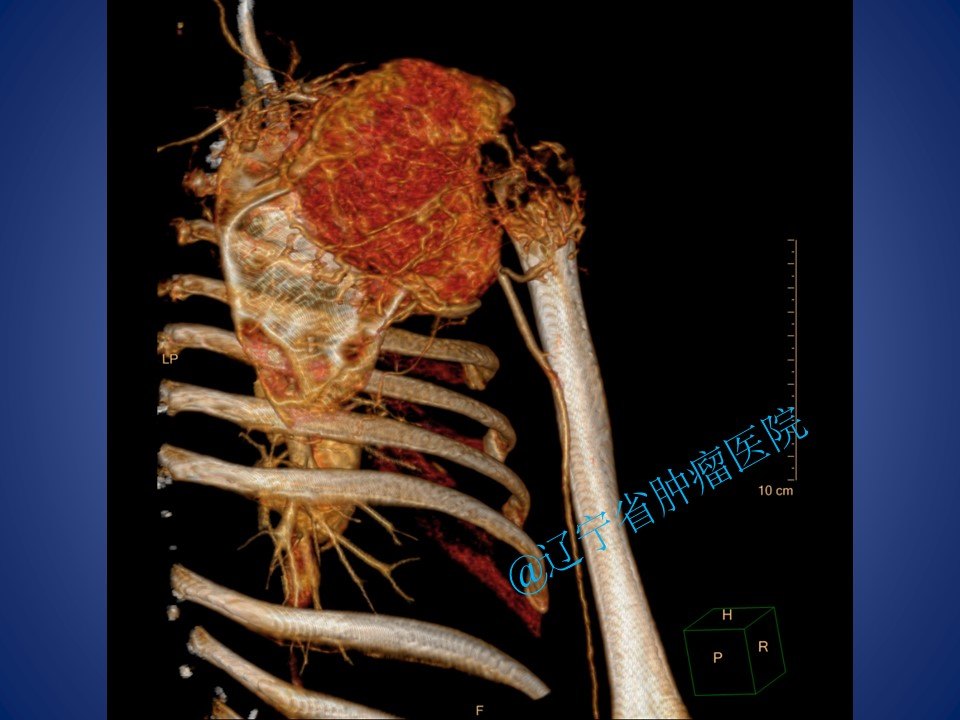

肩胛带骨转移癌旷置手术

肾透明细胞癌骨转移一例